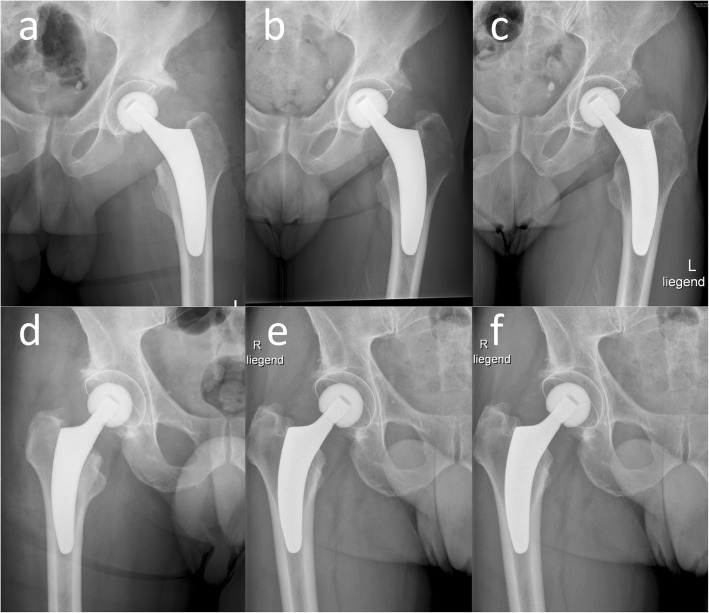

Fig. 4.

Representative cases without and with 3 mm of subsidence. In this figure, a case, in which no subsidence (a–c) and a case, in which 3 mm of subsidence (d–f) was seen up to 5 years postoperative are presented. Postoperative (a and d), 12 months postoperative (b and e) and 5 years postoperative (c and f) a-p x-rays are depicted